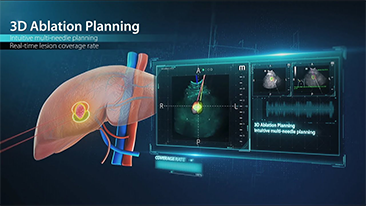

Comment voir le foie au mieux??

L'imagerie de contraste joue un r?le important en cas de lĂŠsions hĂŠpatiques focales, par exemple hĂŠmangiome ou cancer hĂŠpatique. La technologie d'imagerie de contraste UWN+ ultra-large et non linĂŠaire offre une meilleure pĂŠnĂŠtration, un rapport contraste-tissu plus ĂŠlevĂŠ, avec un index mĂŠcanique (IM) plus faible et une observation plus longue du temps de perfusion.